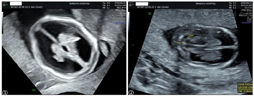

NT超声检查提示:CRL 58 mm,NT 1.4 mm,结构扫查发现双侧侧脑室内脉络丛短小,脉络丛长度/侧脑室长度约0.5,脑干扭曲呈z形,怀疑胎儿脑室扩张及脑干形态异常(图1)。嘱孕妇两周后复查,孕15周超声提示胎儿双侧侧脑室明显扩张,较宽处约11 mm,第三脑室宽约2.3 mm,Z形脑干,小脑横径8.2 mm(小于第1百分位),提示小脑发育不良(图2):双侧侧脑室明显扩张,小脑发育不良,Z形脑干。